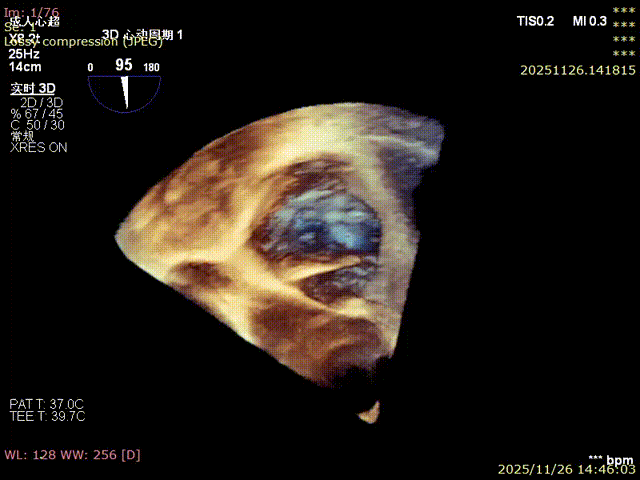

3D image

Annular area: 11.0 cm² (1100 mm²)

Immediate postoperative echocardiographic evaluation showed that tricuspid regurgitation was reduced from severe (4+) to mild (1+), with a 30% reduction in annulus area. No adverse events such as atrioventricular block, valve laceration, or cardiac tamponade occurred intraoperatively or postoperatively. Concurrent right coronary angiography confirmed no compression or distortion of the coronary artery course and normal blood flow perfusion. The patient recovered smoothly after the procedure, and right heart failure symptoms were significantly improved at discharge.